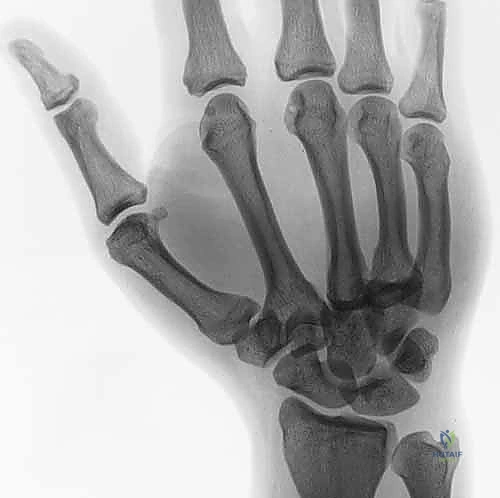

لفهم طبيعة هذه الإصابة، يجب علينا أولاً الغوص في التشريح الدقيق لليد. تتكون اليد من ثلاثة أجزاء عظمية رئيسية:

1. عظام الرسغ (Carpal Bones): وهي 8 عظام صغيرة تشكل قاعدة اليد.

2. عظام المشط (Metacarpal Bones): وهي 5 عظام طويلة تشكل كف اليد.

3. السلّاميات (Phalanges): وهي عظام الأصابع.

مفصل الكربوميتاكاربال هو النقطة التي تلتقي فيها عظام المشط بعظام الرسغ. هذا المفصل ليس متماثلاً في جميع الأصابع:

* المفصل الثاني والثالث (السبابة والوسطى): هي مفاصل صلبة جداً وثابتة، وتعمل كعمود فقري مركزي لليد. حركتها تكاد تكون معدومة لتوفير القوة القصوى أثناء الإمساك بالأشياء.

* المفصل الرابع والخامس (البنصر والخنصر): هي مفاصل أكثر مرونة وتسمح بحركة تتراوح بين 15 إلى 30 درجة. هذه المرونة ضرورية لتشكيل قبضة اليد والقدرة على الإمساك بالأشياء الدائرية أو الأسطوانية.

عند حدوث قوة ضغط هائلة أو التواء شديد، تفشل الأربطة القوية التي تربط هذه العظام، مما يؤدي إلى خلع المفصل. وإذا كانت القوة كافية، فإنها تكسر حافة العظم أثناء خلع المفصل، وهو ما يُعرف بـ كسر وخلع الكربوميتاكاربال (Fracture-Dislocation).